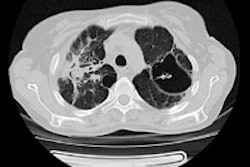

X-ray screening, however, presents its own challenges: There is no radiographic pattern unique or specific to TB, and this is compounded by atypical patterns seen in TB patients with HIV. Moreover, chest x-ray is insufficient as a single tool in the diagnosis and follow-up of the disease.

The introduction of CT, MRI, and PET/CT, as well as whole-body imaging for HIV-associated TB, now promises much for honing detection, assessment, and follow-up, particularly for differential diagnoses, staging, and disease activity. Multislice CT could aid in the assessment of multifocal and multisystem TB. It could also reduce the overdiagnosis of TB, or "false positives" by identifying nontuberculous changes such as calcification and thymus and vascular abnormalities, as Tyurin demonstrated in his presentation through a ductus arteriosus calcification visualized both on CT and x-ray.

Furthermore, lymphadenopathy, often the only radiographic finding in the pediatric patient and, therefore, a hallmark of TB, might be difficult to assess with x-ray if the primary TB changes were only slight. CT therefore was an important tool in risk group pediatric patients as it improves the diagnosis of lymphadenopathy.

However, lymph node assessment with CT in the pediatric TB patient remained problematic, often leading to overdiagnosis of TB due to errors in interpretation and a lack of measurement standards, as well as a lack of standardization in contrast enhancement dose in high-risk patients.